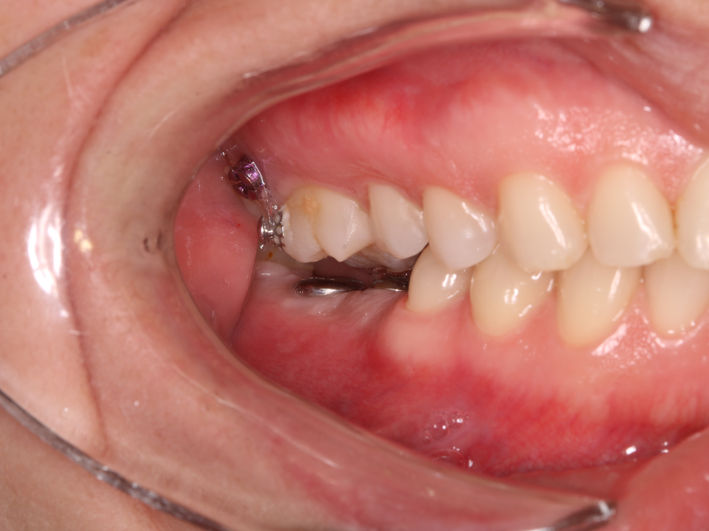

Pacienta se prezinta în cabinet pentru a trata leziunea de la nivelul molarului inferior. Analizând ocluzia observăm absența spațiului suficient pentru o lucrare corectă. Astfel, am aplicat un aparat dentar local cu mini-implanturi pentru a intruza molarul superior si a recâștiga spațiul necesar.

După tratamentul ortodontic și câștigarea spațiului necesar am preparat minim dintele, am luat amprentă și tehnicianul a realizat un onlay din material compozit. Acesta a fost lipit sub izolare cu digă.